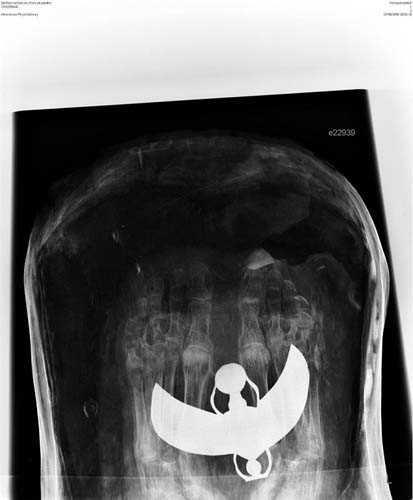

2. Fotoğrafta gördüğünüz Mısır mumyasının CT taraması, uygarlığının gizemlerini çözmeye yardımcı olacak.

Fotoğrafta gördüğünüz Mısır mumyasının CT taraması, uygarlığının gizemlerini çözmeye yardımcı olacak.

3. İngiltere'de Dr. Abeer Helmi, bu teknolojiyi kullanarak tarihin derinliklerinden gelen lahitleri açarken zarar verme riski olmadan içeriğini görüntüleyebiliyor.

İngiltere'de Dr. Abeer Helmi, bu teknolojiyi kullanarak tarihin derinliklerinden gelen lahitleri açarken zarar verme riski olmadan içeriğini görüntüleyebiliyor.

4. Dr. Helmi, British Museum'dan özel izinle aldığı yedi mumya üzerinde bu cihazı test etti.

Dr. Helmi, British Museum'dan özel izinle aldığı yedi mumya üzerinde bu cihazı test etti.

5. Yapılan taramalar M.Ö. 900 civarında Mısırlıların sağlığı ve davranışları konusunda önemli ipuçları verdi.

Yapılan taramalar M.Ö. 900 civarında Mısırlıların sağlığı ve davranışları konusunda önemli ipuçları verdi.